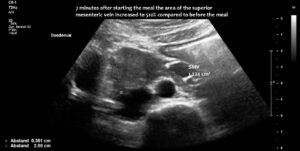

Enlargement of the superior mesenteric vein can be observed as early as five minutes after eating, progressing to fivefold enlargement of the transsectional area after seven minutes.

The superior mesenteric vein appeared normal when the stomach was empty, but showed enormous 5-fold enlargement of its transsectional area after food was consumed. The enlarged vein prevented food from passing across the aorta, as the stomach pushed the superior mesenteric vein against the duodenum, narrowing the passage to such an extent that the descending duodenum enlarged to 38 mm (the usual width is less than 20 mm). The patient reported substantial pain in the area of the distended duodenum, below the right rib cage.